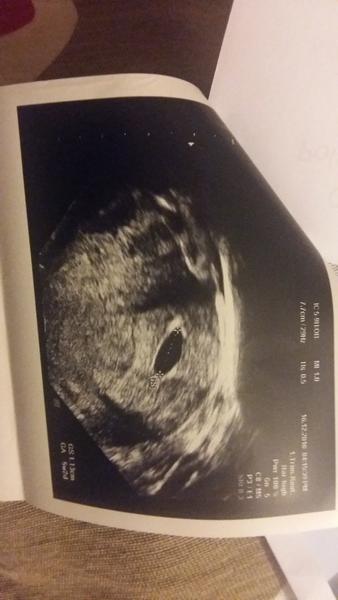

@patkaamirko ja som mala v stredu 9mm to bolo presne 5tt0 🙂 tak to máš dobre 🙂 hej po sone môžeš mať viac krvavý výtok je to prasknutia cievka kedze v tehotenstve máš všetko dole viac prekrvene 🙂 🙂 nemaju strach hlavne teda kludovy režim a podloz si nohy aspoň dvoma vankusmi 🙂

@eleonora2705 krasna fotecka a super, ze je vsetko ako ma byt! 😉 ...Gratulujem a prajem zdrave tehulkovanie 😀🤰

@patkaamirko krásna fotecka tak to ti zodpovedá veľkosť máš dobrú 🙂 uvidíš o tyzden ako sa to zmení na krásne bábätko zo ❤